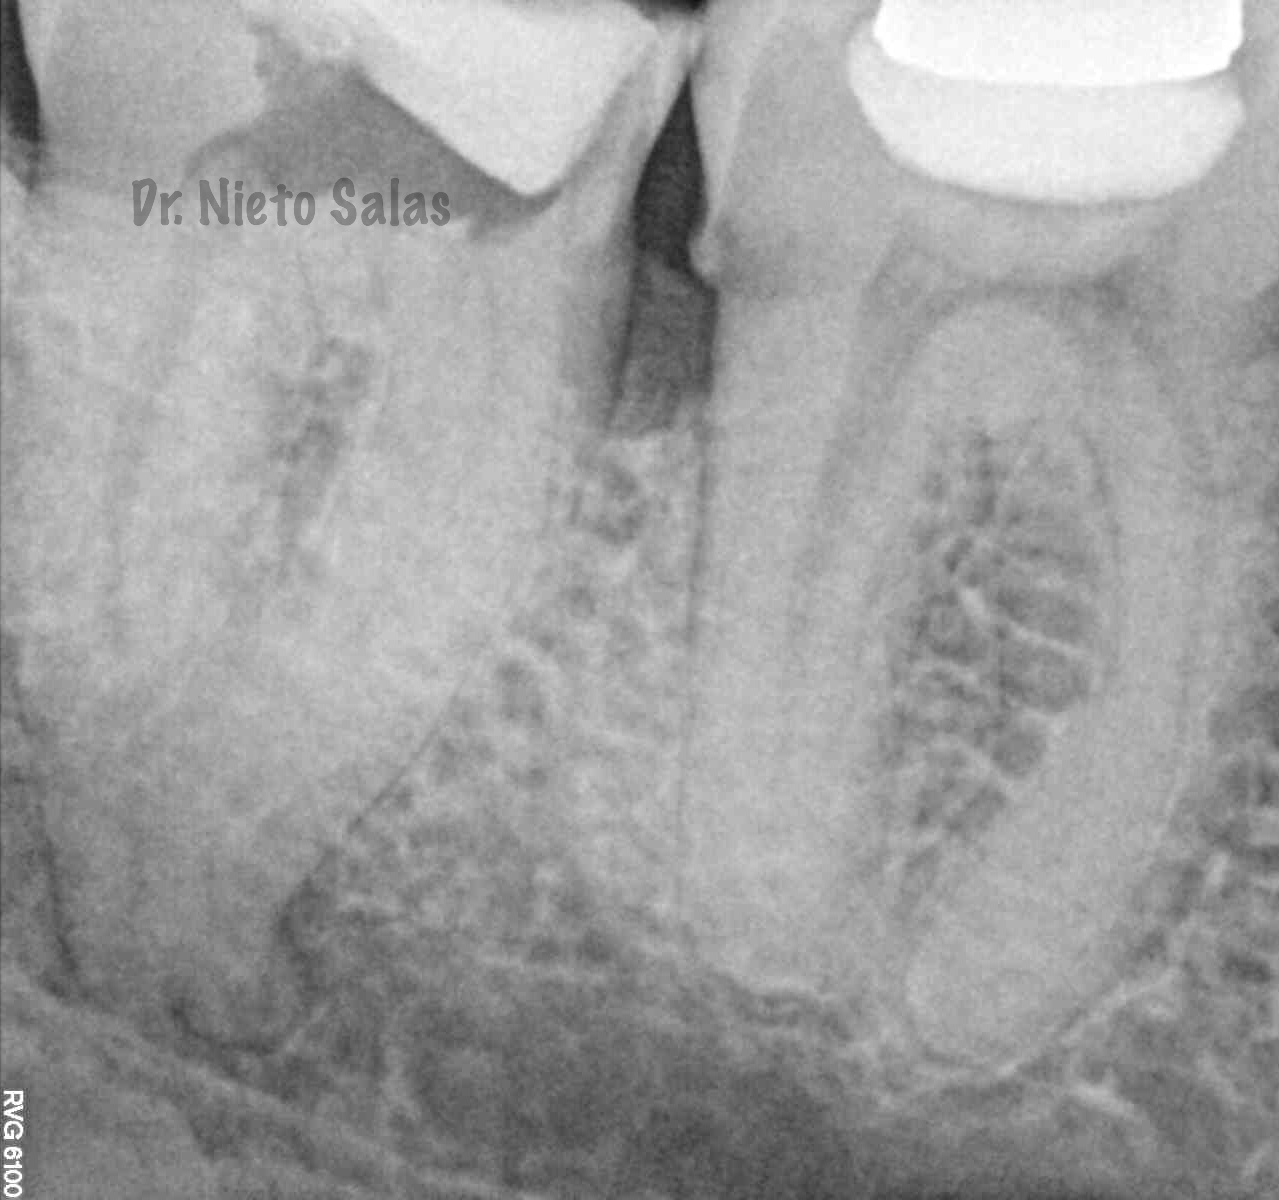

Bueno , ante esta piezas, que presentan una periodontitis apical crónica en la 4.7 y una pulpitis irreversible en la 3.7 nos disponemos a realizar le tratamiento de conductos.

En esta entrada vamos a ver que tan diferentes pueden ser dos tratamiento de conductos de dos segundos molares inferiores, cuya anatomía debemos valorar antes de empezar el tratamiento.